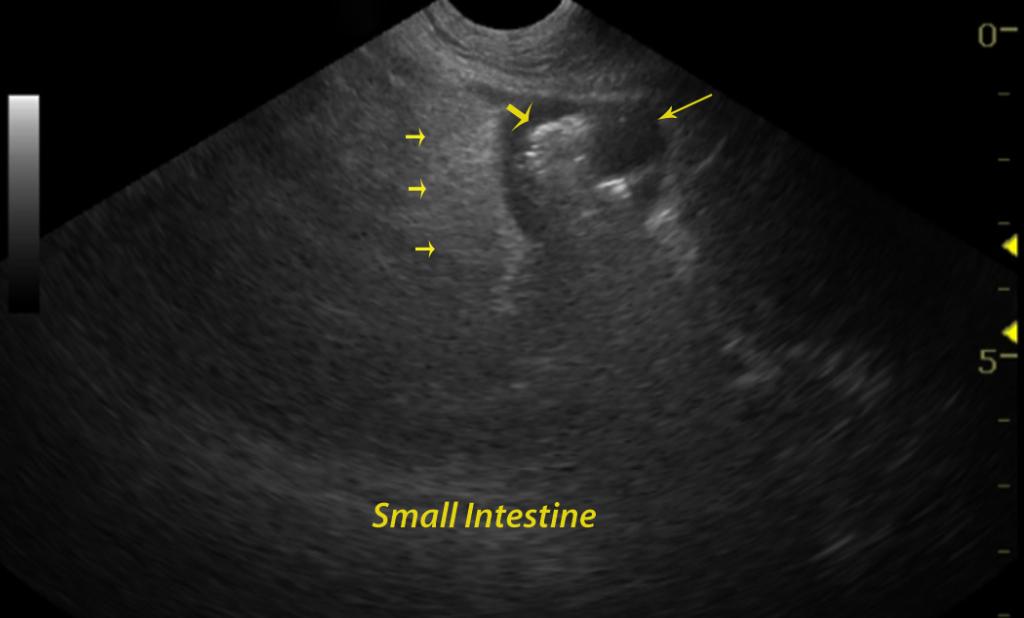

A 10-year-old MN Golden retriever was presented for lethargy and inappetence. No abnormalities were noted on the physical exam. The following day hematochezia was reported. CBC was within normal limits. Blood chemistry profile revealed elevated cholesterol , elevated total bilirubin, elevated direct bilirubin, hypoproteinemia, hypoalbuminemia, and hypocalcemia. Urinalysis revealed hematuria and bilirubinuria.